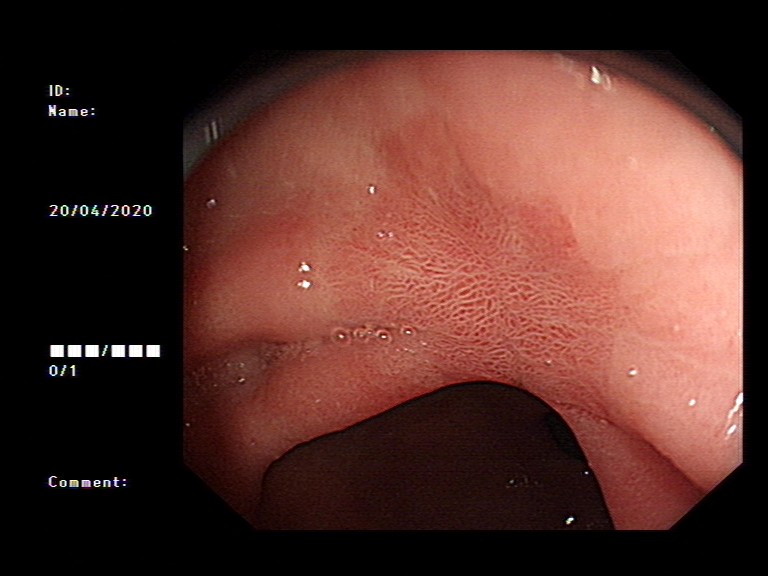

2020年1月,元旦刚过,大家都还沉浸在新年的喜悦中,来自隆安县的张阿姨一家却一筹莫展,张阿姨今年55岁,半年前开始出现上腹部胀痛不适,在当地医院一直按“慢性胃炎”服用中药及西药治疗,症状时好时坏。为了进一步治疗,来到我院就诊,内镜中心袁海锋主任亲自为其进行了无痛胃镜检查,经认真仔细观察发现胃内一处凹陷型病变,进一步行精细胃镜检查后,初步判断为早期胃癌病灶,而且病变侵犯深度局限在粘膜层内。经过与张阿姨及家属详细沟通后,决定用内镜下微创手术为其治疗。在内镜下确定病变边界后,顺利行内镜下粘膜剥离术(ESD)将病变完整切除。术后标本病理提示:早期胃癌(中分化管状腺癌)。治疗后一周,恢复良好,顺利出院,至今随访未诉明显不适。对于张阿姨一家来说,得了胃癌很不幸,但不幸中的万幸,她的胃癌被我们早期及时发现并完成了内镜下切除,避免进展为中晚期胃癌,使原本不富裕的家庭再雪上加霜。

图4 术后三月、6月复查胃镜

我们再来看一组胃镜图片,由胃溃疡到胃癌的过程(图片来源于网络)。患者未按医生医嘱,定期复查胃镜活检,最后进展为晚期胃癌。